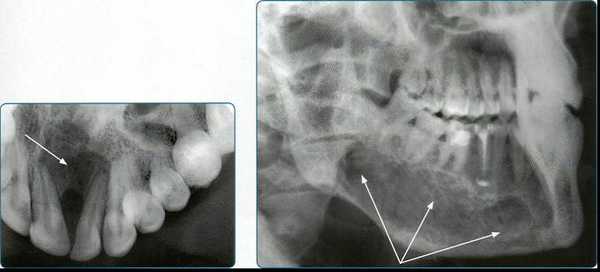

Методы рентгенодиагностики в стоматологии

Рентгенологические методы исследования являются ведущими в диагностике заболеваний челюстно-лицевой области, что обусловлено их достоверностью и информативностью. Методы рентгенодиагностики нашли широкое применение в практике терапевтической стоматологии (для выявления заболеваний пери- и пародонта); в ортопедической стоматологии (для оценки состояния сохранившихся зубов, периапикальных тканей, пародонта), что определяет выбор ортопедических мероприятий. Востребованы рентгенологические методы и челюстно-лицевой хирургией в диагностике травматических повреждений, воспалительных заболеваний, кист, опухолей и других патологических состояний.

1. Внутриротовая контактная рентгенография

Основой рентгенологического исследования при большинстве заболеваний зубов и пародонта по-прежнему служит внутриротовая рентгенография.

На одном снимке можно получить изображение не более 2-3 зубов

4. Панорамная томография

Более трех десятилетий назад в арсенал рентгенодиагностики заболеваний зубочелюстной системы, ЛОР-органов и других отделов черепа вошла панорамная рентгенография. При этом методе исследования аппликатор рентгеновской трубки вводят в рот пациента, а кассета располагается вокруг верхней или нижней челюстной дуги. В обоих случаях пациент придерживает кассету с наружной стороны ладонями, плотно прижимая ее к мягким тканям лица.

Прямые панорамные рентгенограммы имеют преимущество перед внутриротовыми снимками по богатству деталями изображения костной ткани и твердых тканей зубов. При минимальной лучевой нагрузке они позволяют получить широкий обзор альвеолярного отростка и зубного ряда, облегчают работу рентгенолаборанта и резко сокращают время исследования. На этих снимках хорошо видны полости зуба, корневые каналы, периодонтальные щели, межальвеолярные гребни и костная структура не только альвеолярных отростков, но и тел челюстей. На панорамных рентгенограммах выявляются альвеолярная бухта и нижняя стенка верхнечелюстной пазухи, нижнечелюстной канал и основание нижнечелюстной кости.

На основании панорамных снимков диагностируют кариес и его осложнения, кисты разных типов, новообразования, повреждения челюстных костей и зубов, воспалительные и системные поражения. У детей хорошо определяется состояние и положение зачатков зубов.